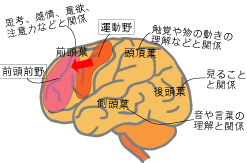

脳の構造 大脳を4つの領域に分けるランドマーク

脳の構造 大脳を右脳と左脳に分ける脳の溝

脳の構造と役割 子供の脳の発達のための 脳育jp 子どもに健やかな成長と健全な発達を